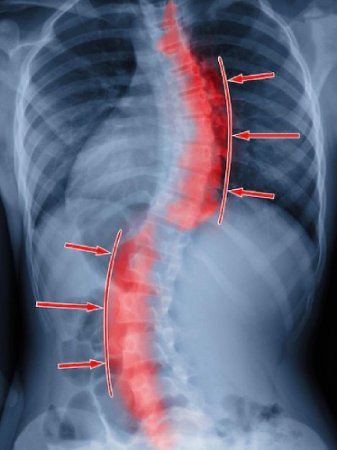

Scoliosis is more than just a “curved spine.” It is a condition where the spine curves sideways, often in a “S” or “C” shape, also known as lateral curvature of spine. While scoliosis can appear at any age, it is most commonly noticed in teenagers during growth spurts. Females are more prone to scoliosis than males. Early awareness, timely intervention, and proper management can make a significant difference in maintaining mobility, function, and quality of life.

- Visible curve in the spine